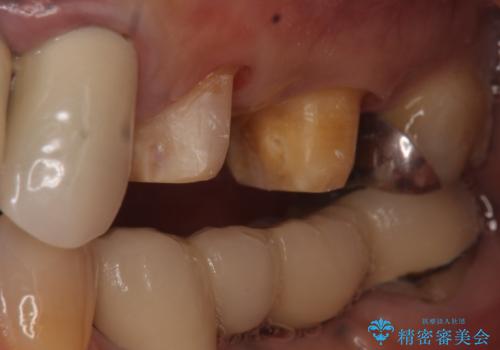

- 昔治療した左上56の延長ブリッジをきちんと治療しなおしたいといらっしゃった方の症例です。

古いブリッジを除去後、オールセラミッククラウンによる補綴を行いました。